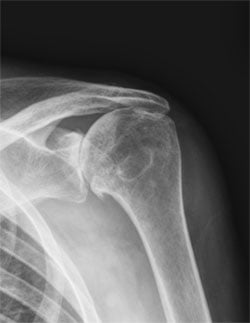

What is the difference between reverse shoulder replacement and regular shoulder replacement?

The main difference is how the artificial joint is positioned in the shoulder. In a regular or traditional shoulder replacement (called an anatomic shoulder replacement), the damaged parts of the shoulder joint – the ball and socket – are replaced with artificial ones in the same positions as in the natural joint. In a reverse shoulder replacement, the positions of the ball and socket are switched. The artificial ball is attached to the socket side of the joint and the artificial socket is placed where the natural ball used to be.

By reversing the positions of the ball and socket, the surgery allows different muscles to take over the function of the damaged ones, improving the shoulder's movement and stability. This changes how the shoulder rotates at its center and utilizes different muscles, such as the deltoid, to provide better stability and movement, especially for individuals with compromised rotator cuff muscles or complex shoulder conditions.